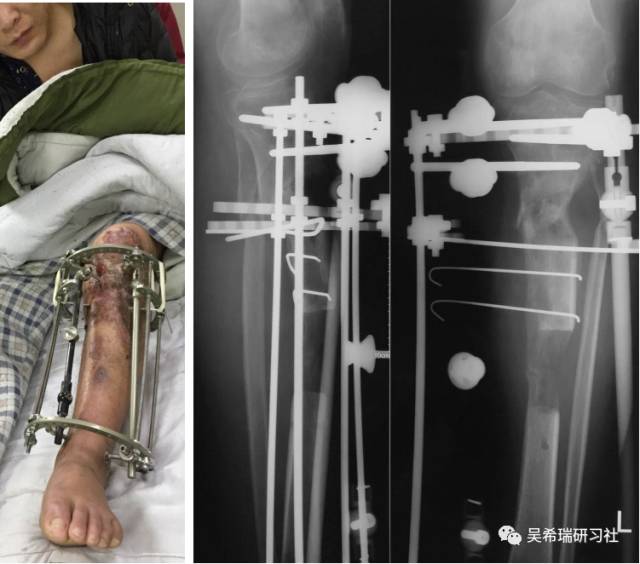

车祸伤多发伤胫骨近端开放骨折软组织缺损右上肢截肢

TIPS:开放骨折外固定游离植皮缩小伤口搬移+半开放植骨半开放植骨=骨水泥技术+开放植骨+骨搬移横向、前后调整搬移骨块下地走路刺激骨愈合早期关节功能锻炼